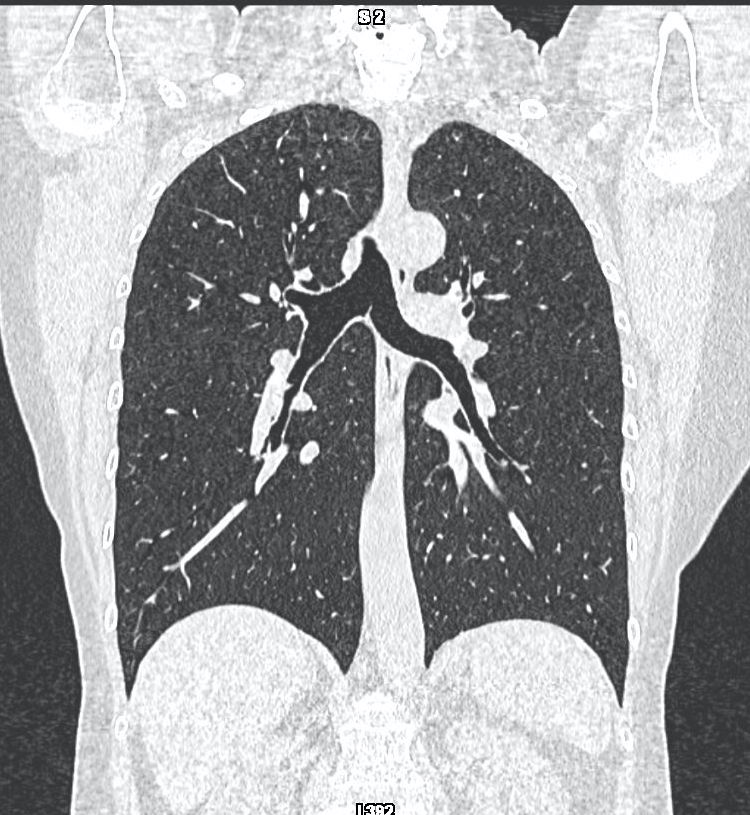

Il s’agit d’un examen d’imagerie médicale qui utilise les rayons X pour visualiser les parties du corps humain. A la différence de la radiographie standard, il permet une analyse en coupes fines du corps.

Cet examen permet à votre médecin d’avancer dans sa démarche diagnostique quand l’examen clinique ne suffit pas. Il peut être complémentaire des autres modalités d’imagerie que sont l’échographie, l'IRM, la scintigraphie,...